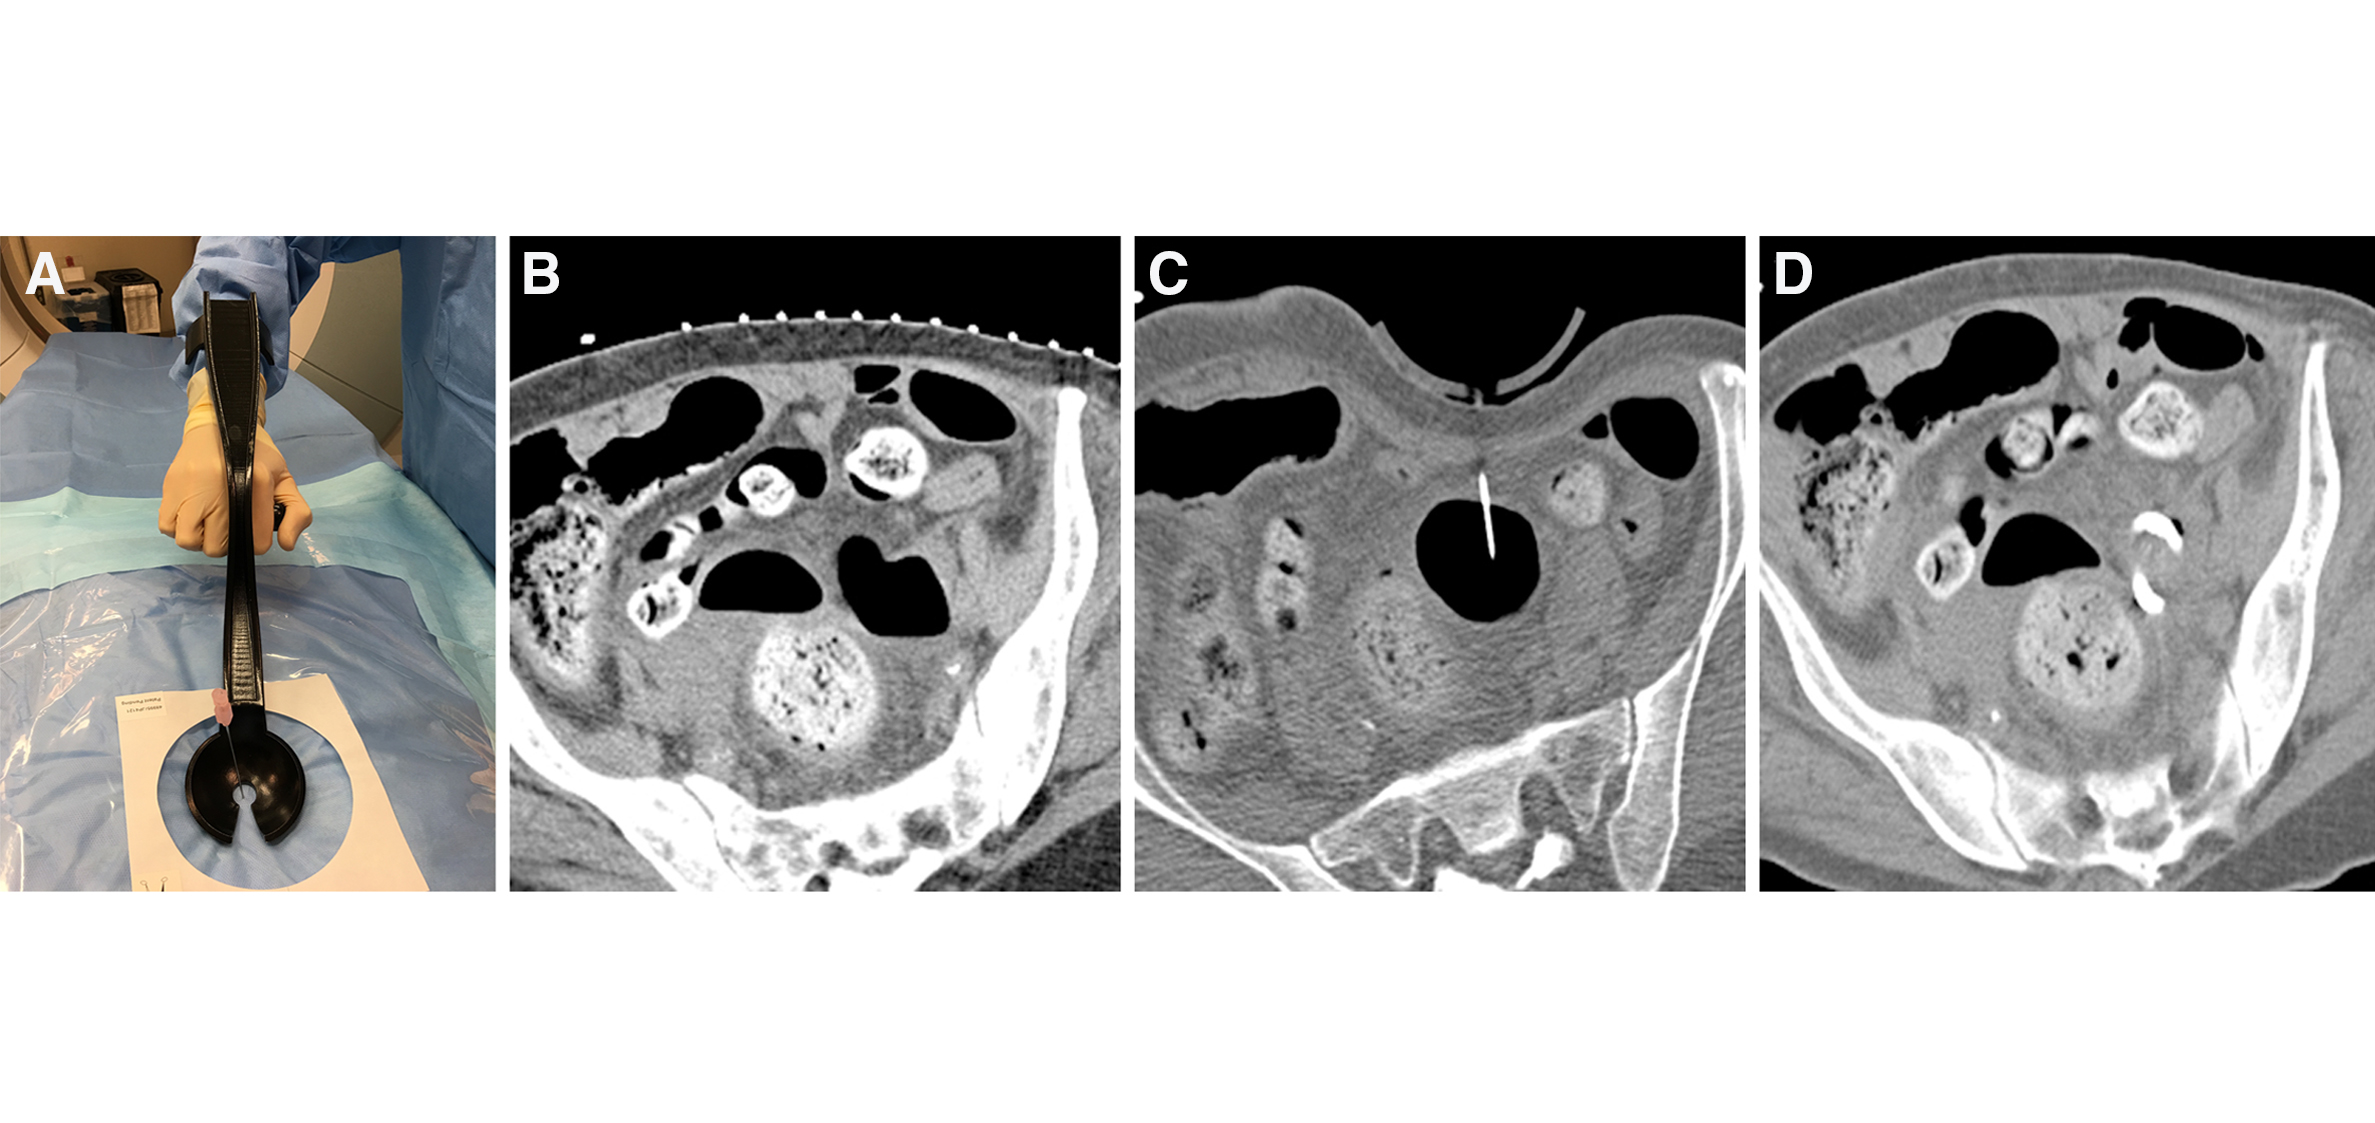

I am a computational designer, architect and geometry junkie - currently a research fellow at Harvard University’s Wyss Institute for Biologically Inspired Engineering studying geometry-function relationships in biological composites and fabricating their synthetic analogs through additive manufacturing. I also work at Brigham and Women’s hospital’s surgical planning lab

designing hardware for sizing heart valve prosthesis and image guided surgery. My interests include computational geometry, additive manufacturing and developing tools for the web.